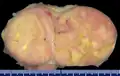

Additional images